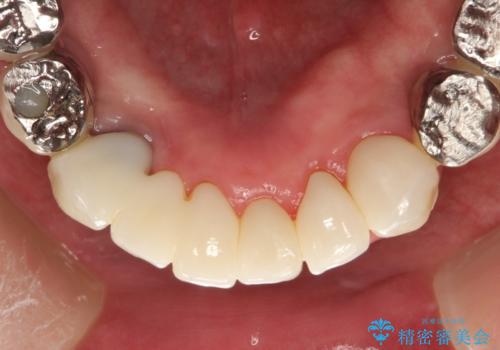

虫歯だらけ、歯周病 崩壊した口腔の再建 フルマウスリコンストラクション

費用・時間は多大にかかりましたが、今後しっかりと咬んで生活することができるでしょう。

かみ合わせの力が非常に強く、夜間の歯ぎしり・食いしばりもひどかったため、奥歯はメタルオクルーザルの設計でかぶせ物を製作しています。

かぶせ物の種類:PFZ / PFM metal occlusal